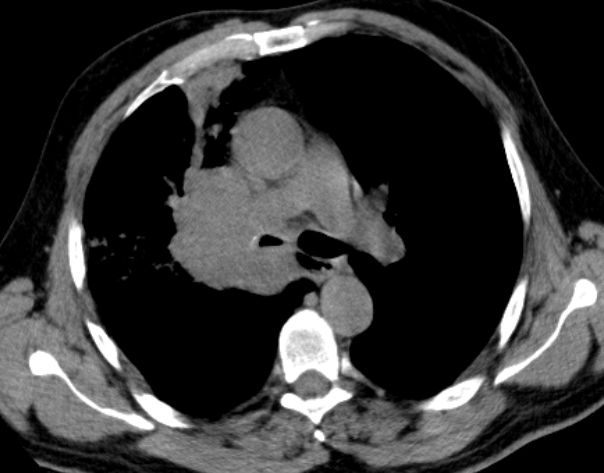

zentrales, kleinzelliges Lungenkarzinom rechter OL mit Infiltration des Mediastinums T4 N3 M1 oss ? 68jährige Patientin im reduzierten AZ und normalen EZ. Unsicherer Gang bei Kreislaufstörungen. Belastungsdyspnoe. Deutliche Leistungsschwäche. Supraklavikulargruben: links frei, rechts auffälliger Tastbefund. ![]() |

![]() |